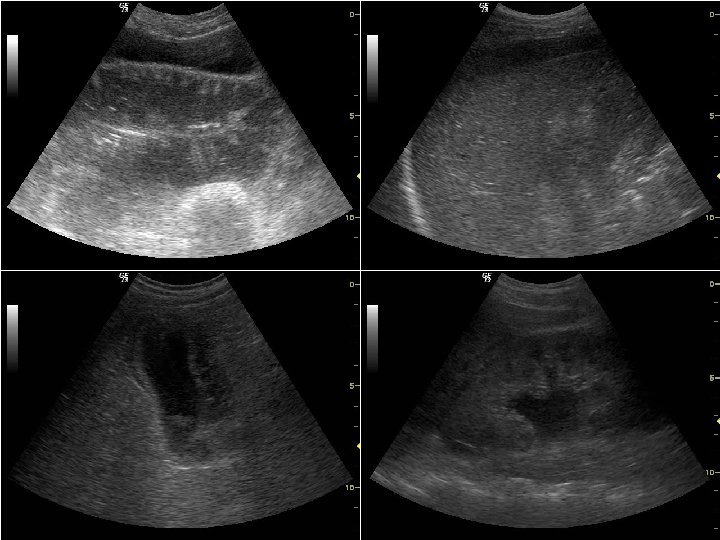

ECO SEPSI LA FONTE • L’ecografia in valutazione primaria e secondaria (testapiedi) consente di identificare il 75 -85% delle fonti settiche, congiuntamente alla clinica • In caso di infezione di origine toracica si riscontra di regola una sindrome focale (versamento pleurico, impegno interstiziale localizzato, consolidamento) • Nell’addome il riscontro di versamento endoperitoneale non localizzato (con o senza gas) è suggestivo per una patologia diffusa, mentre le infezioni focali presentano quadri specifici (indicativi per colecistite, diverticolite, ascessi, ostruzione delle vie urinarie, ecc. ) • Altre infezioni focali (osteo-articolari o dei tessuti molli) sono più facilmente evidenti – l’ecografia può fornire elementi aggiuntivi (p. es. presenza di gas)

SEPSI FASTCRASH SEPSI DISPNEA O DOLORE TORACE ECOtorace IMPEGNO DIFFUSO PARENCHIMALE IMPEGNO FOCALE PARENCHIMALE VERSAMENTO PLEURICO Rx. Torace Punt Esplor INTERESSAMENTO SECONDARIO POLMONITE O ASCESSO EMPIEMA Supporto Terapia medica Drenaggio Terapia medica Supporto Terapia medica

SEPSI FASTCRASH SEPSI DOLORE ADDOME DISURIA ECOaddome IDRONEFROSI PATOLOGIA RENALE PATOLOGIA FOCALE VERSAMENTO DIFFUSO TCAddome Punt Esplor PIELONEFRITE IVU con OSTRUZIONE COLECISTITE DIVERTICOLITE PANCREATITE PERFORAZIONE ISCHEMIA PERITONITE Terapia medica Chirurgia Drenaggio VU Drenaggio Terapia medica